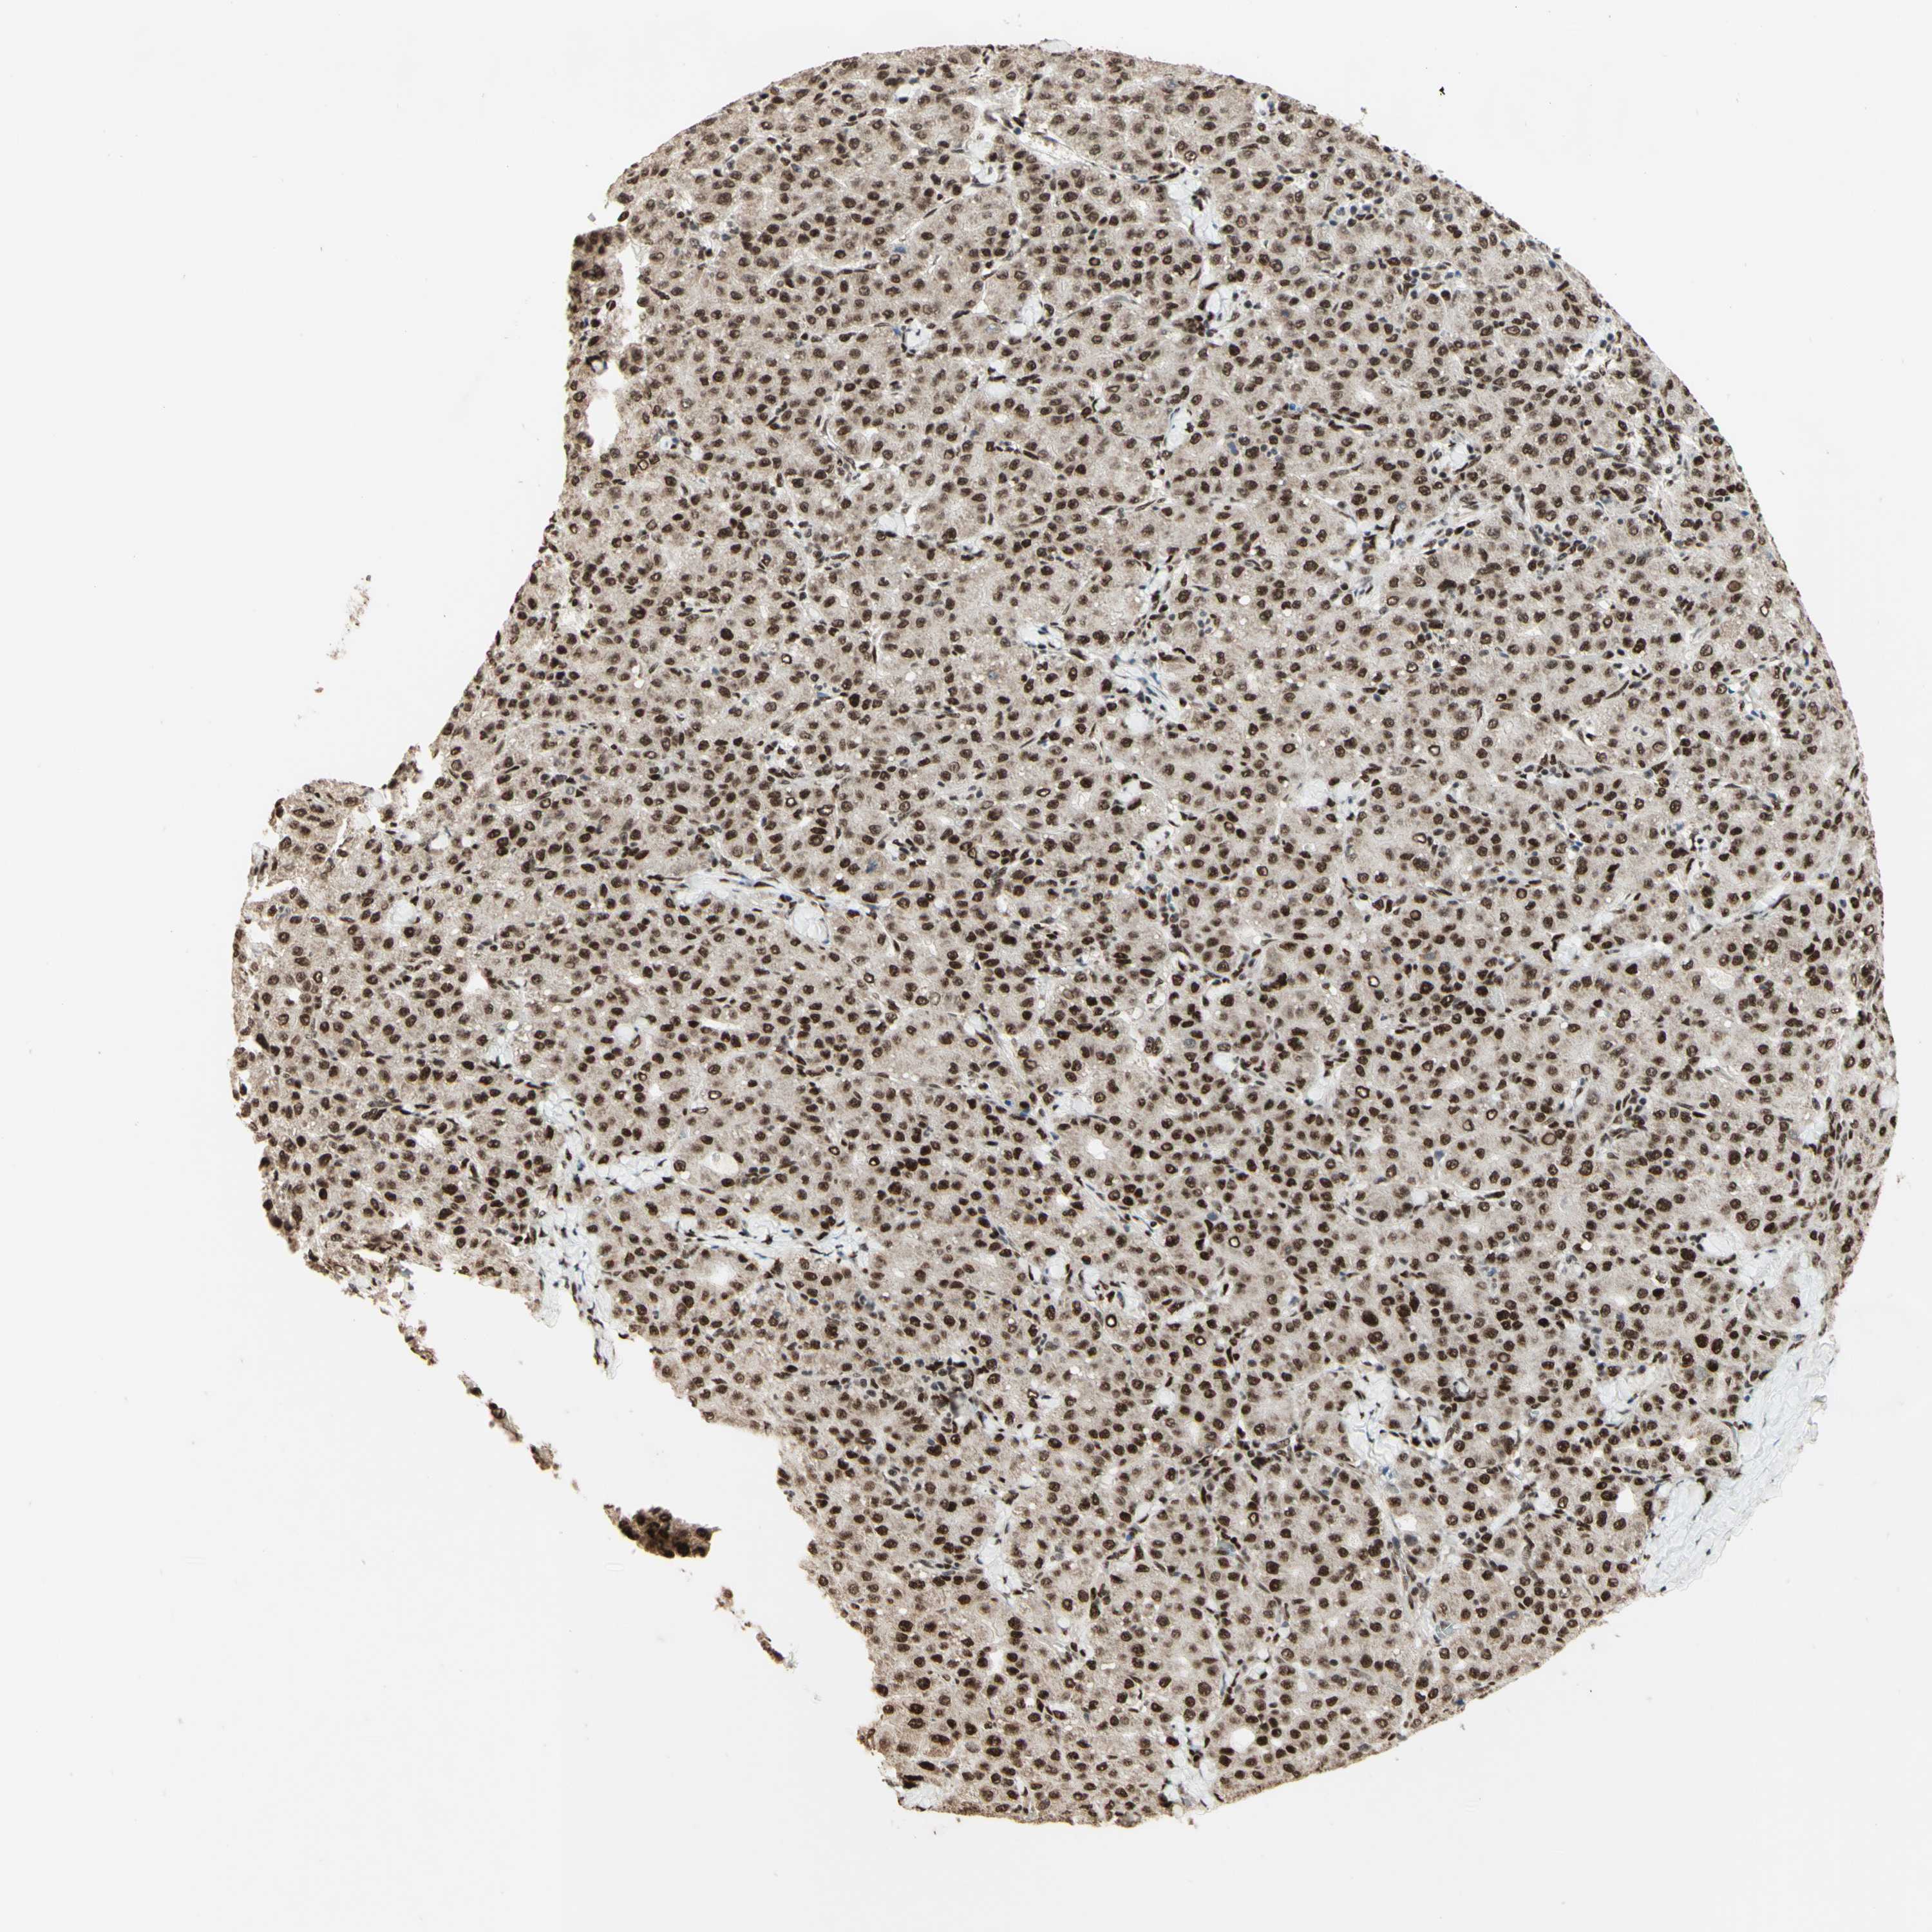

LIVER CANCER - Protein expressioni

A mouse-over function shows sample information and annotation data. Click on an image to view it in a full screen mode. Samples can be filtered based on level of antibody staining by selecting one or several of the following categories: high, medium, low and not detected. The assay and annotation is described here.

Antibody stainingi

Antibody staining in the annotated cell types in the current human tissue is reported as not detected, low, medium, or high, based on conventional immunohistochemistry profiling in selected tissues. This score is based on the combination of the staining intensity and fraction of stained cells.

Each image is clickable and will lead to virtual microscopy that enables deeper exploration of all samples and also displays staining intensity scores, fraction scores and subcellular localization as well as patient and tissue information for each sample.

Antibody HPA004248

Antibody CAB010435

Staining

High

Medium

Low

Not detected

Intensity

Strong

Moderate

Weak

Negative

Quantity

>75%

75%-25%

<25%

None

Location

Nuclear

Cytoplasmic/membranous

Cytoplasmic/membranous,nuclear

Cholangiocarcinoma

Carcinoma, Hepatocellular, NOS